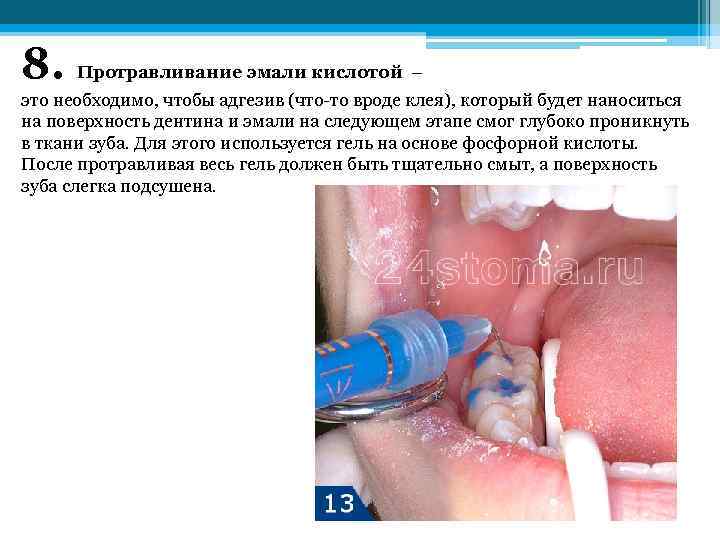

8. Протравливание эмали кислотой – это необходимо, чтобы адгезив (что-то вроде клея), который будет наноситься на поверхность дентина и эмали на следующем этапе смог глубоко проникнуть в ткани зуба. Для этого используется гель на основе фосфорной кислоты. После протравливая весь гель должен быть тщательно смыт, а поверхность зуба слегка подсушена.

8. Протравливание эмали кислотой – это необходимо, чтобы адгезив (что-то вроде клея), который будет наноситься на поверхность дентина и эмали на следующем этапе смог глубоко проникнуть в ткани зуба. Для этого используется гель на основе фосфорной кислоты. После протравливая весь гель должен быть тщательно смыт, а поверхность зуба слегка подсушена.